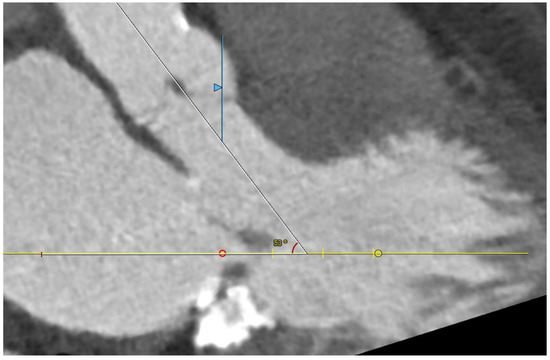

Five observational studies have been published since 2017 exploring the safety and efficacy of ViMAC, all of them with aortic balloon-expandable bioprosthesis in prohibitive surgical risk patients [17,18,19,20,21]. Their designs and main results are summarized in Table 1. To note, the ViMAC procedure shows worse results in terms of technical success and short- and mid-term outcomes than those of ViV and ViR. Indeed, ViMAC is the most challenging percutaneous scenario of all types of TMVR. Mortality at the one-year follow-up is high (around 50%), underscoring the importance of patient selection and of performing these interventions in experienced centers. When comparing the three approaches of TMVR for ViMAC, transatrial appears to have the best results, with one-year rates of mortality at 35% (25% in the latest series) [16,22,23], compared to those of transapical (57%) and transseptal (63%), and higher technical success rates (89% vs. 71% and 65%, respectively). The most important adverse event is the obstruction of the LVOT, with a hazard ratio for mortality of 2.87 (95% confidence interval 1.66–4.96) [19], so this must always be anticipated by a preprocedural CT. An area below 170 mm2 in the LVOT once the valve is implanted (“neo-LVOT”) is highly predictive of this complication (Figure 6) [13]. Other important CT parameters include the angle between the aorta and the LV axis (Figure 7), mitral annulus dimensions (Figure 8), and 2D- or 3D-derived virtual reconstructions (Figure 6).

Figure 7.

Angle between the aortic and the left ventricular centerlines (aorto-mitral angulation, 53o), predictive of left ventricular outflow tract obstruction.